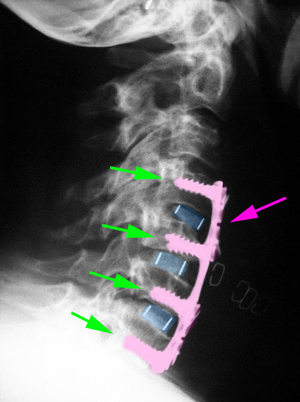

Περιγραφή Η έκταση της σπονδυλοδεσίας και ο τρόπος με τον οποίο πραγματοποιείται εξαρτώνται από το είδος και το μέγεθος της βλάβης που πρέπει να αναταχθεί. Στην εκφυλιστική νόσο προηγείται της σπονδυλοδεσίας η αυχενική δισκεκτομή, σε ένα ή περισσότερα επίπεδα της αυχενικής μοίρας της σπονδυλικής στήλης. Η προσπέλαση είναι όμοια. Στη θέση του δίσκου(-ων) που αφαιρούνται τοποθετείται ένας κλωβός, κατασκευασμένος συνήθως από ειδικό πολυμερές πλαστικό, ο οποίος περιέχει στο κέντρο του οστικό μόσχευμα. Αυτό διατηρεί ή αυξάνει το ύψος του μεσοσπονδυλίου διαστήματος και διανοίγει τα νευρικά τρήματα. Σε ένα ορίζοντα μερικών μηνών στη θέση του οστικού μοσχεύματος δημιουργείται καινούργιο οστό το οποίο συνενώνει τους άνω και κάτω του μοσχεύματος σπονδύλους. Ενισχυτικά της παραπάνω αρθροδεσίας, ιδιαίτερα όταν πρόκειται να αφαιρεθούν παραπάνω τους ενός αυχενικοί δίσκοι, τοποθετείται μια μεταλλική πλάκα στην πρόσθια επιφάνεια των σπονδύλων η οποία στερεώνεται με βίδες σε αυτούς, προκειμένου να επιτευχθεί άμεση σταθεροποίηση. Στην τραυματική αστάθεια του αυχένα η επέμβαση είναι ουσιαστικά ίδια με την διαφορά ότι σε λίγες περιπτώσεις μπορεί να μην απαιτείται δισκεκτομή και η σπονδυλοδεσία να αποτελείται μόνο από την πρόσθια πλάκα και τις βίδες. Στην διάβρωση των σπονδύλων από όγκο, η επέμβαση συμπεριλαμβάνει και την αφαίρεση της χωροκατακτητικής εξεργασίας και αυτό συνήθως συνεπάγεται και αφαίρεση μέρους του σώματος του σπονδύλου. |

Πρόσθια αυχενική δισκεκτομή και σπονδυλοδεσία με κλωβό από PEEK (μπλέ). |

Πρόσθια αυχενική δισκεκτομή Α4-Α5, Α5-Α6, Α6-Α7 και σπονδυλοδεσία με κλωβούς από PEEK (μπλέ) και πλάκα με βίδες Α4-Α7 (ροζ) |